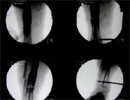

Intra

Op

Acute correction with fixator assisted nailing

Progress